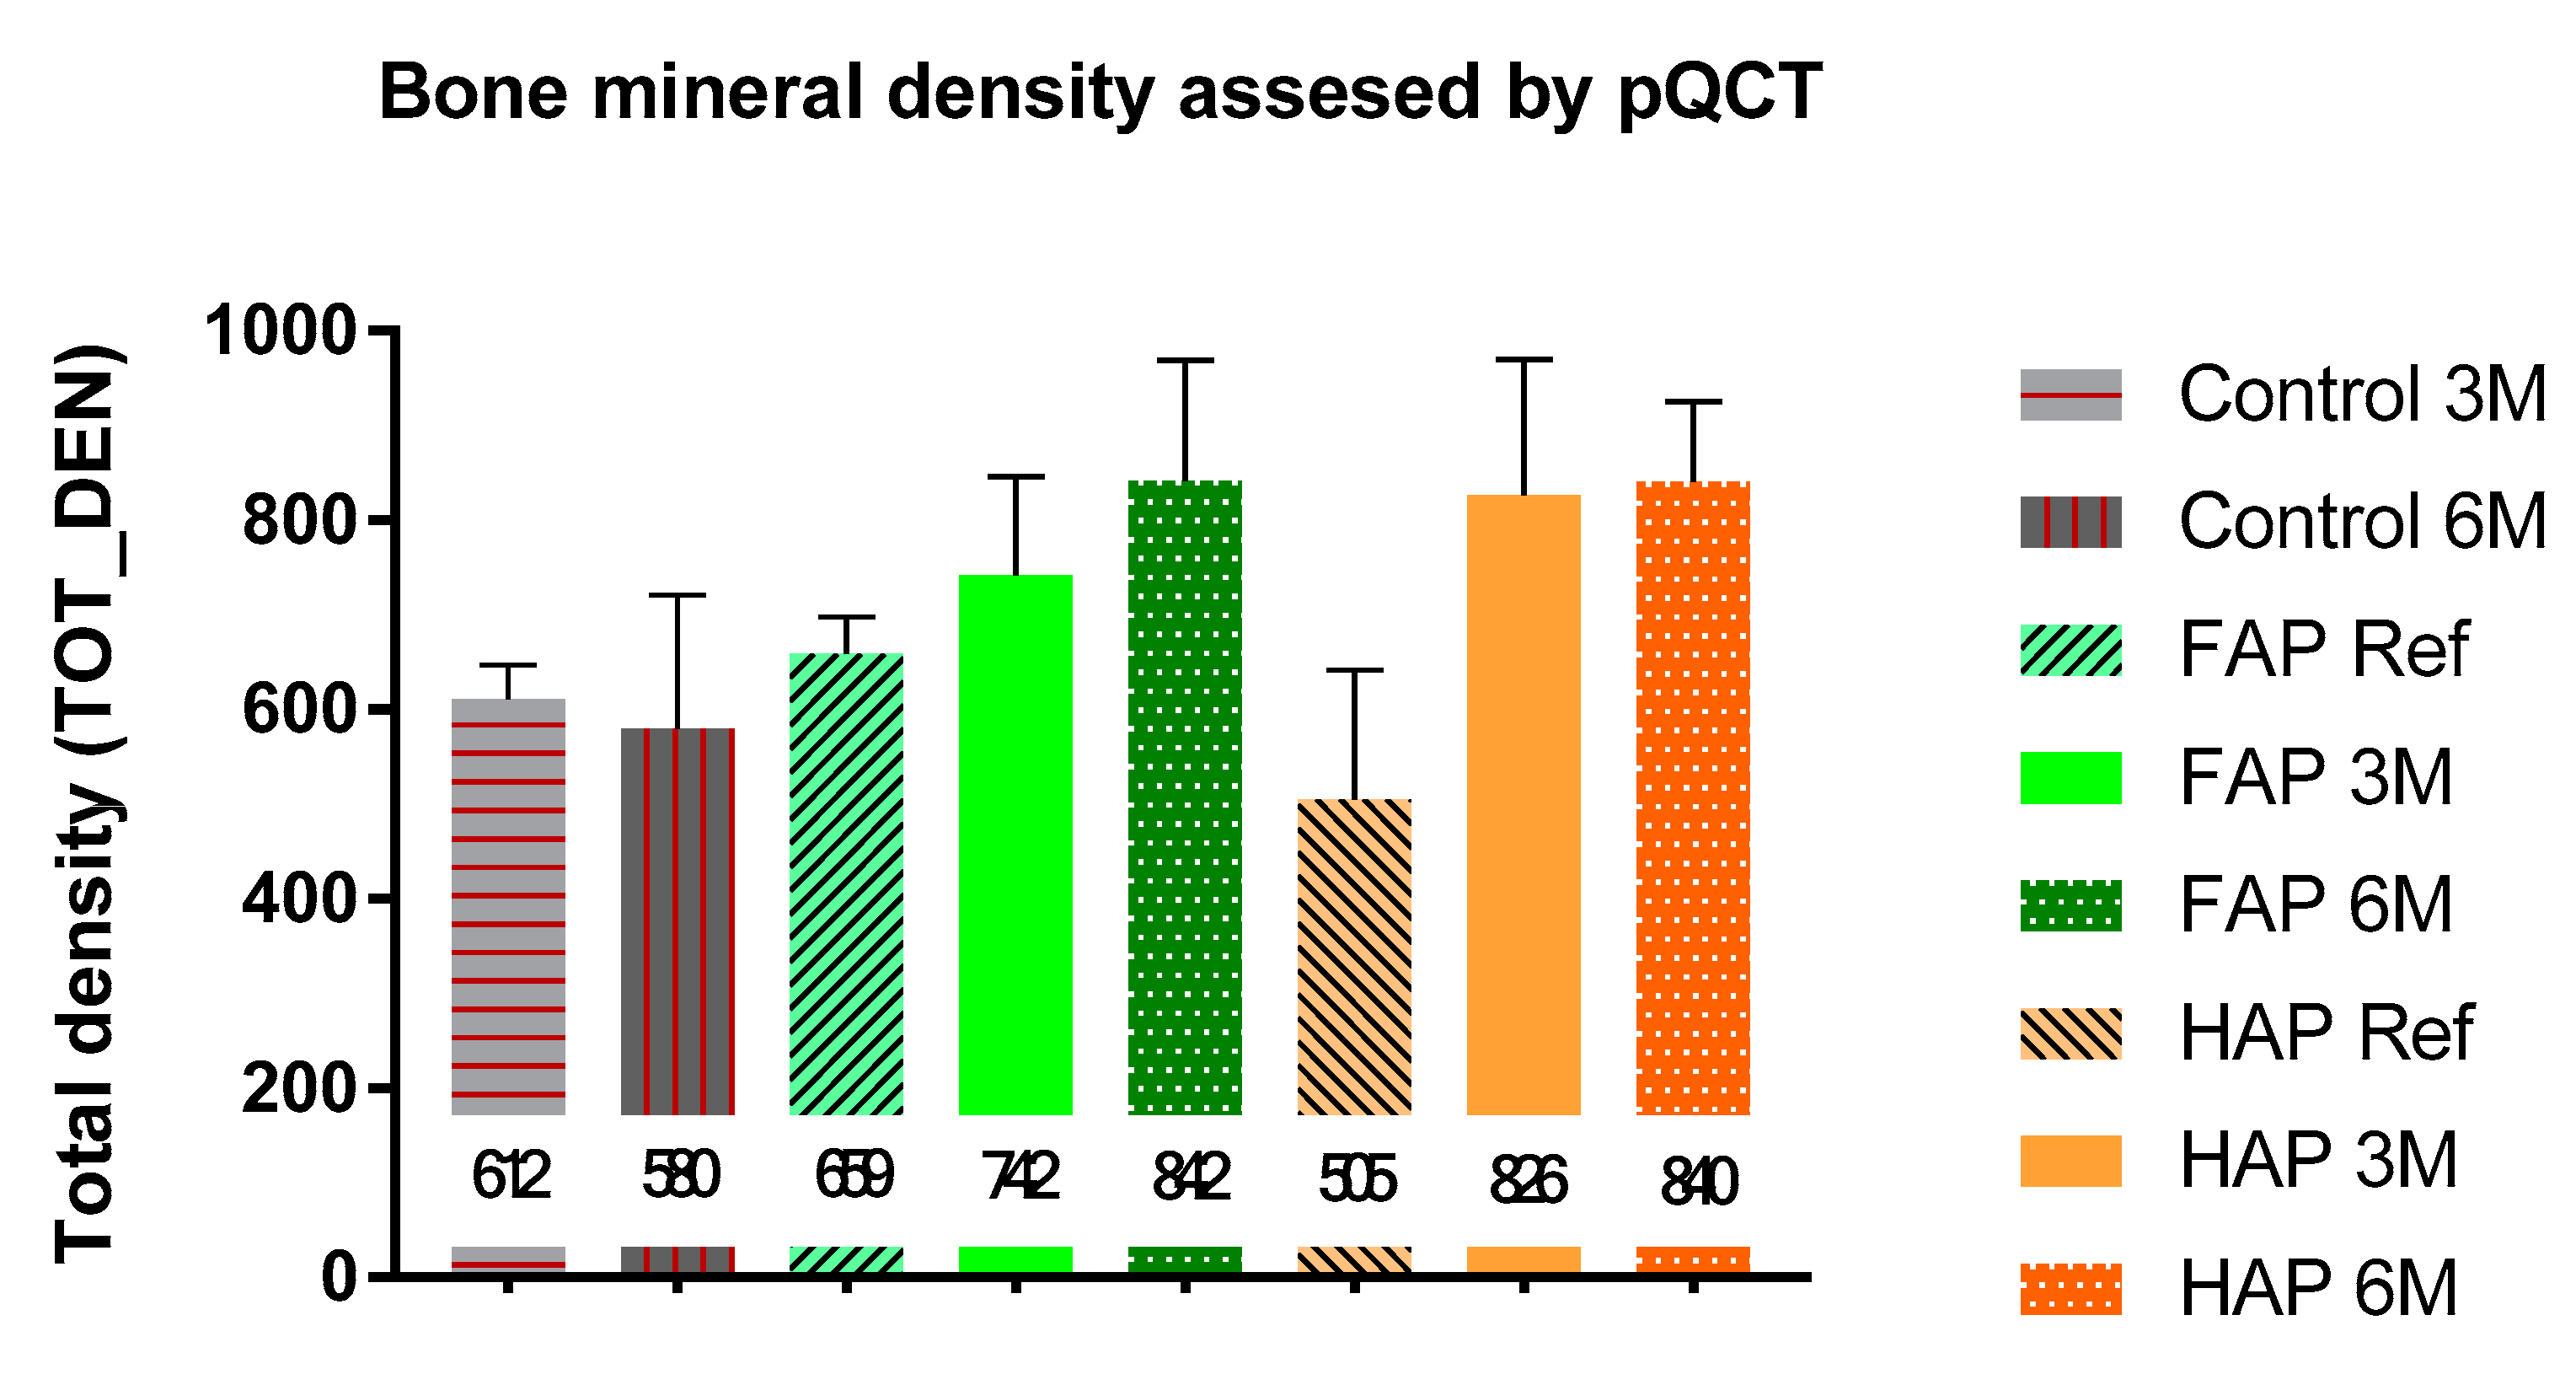

2.4.2. Peripheral Quantitative Computed Tomography (pQCT)

3.2. Quantitative Analysis of Bone Substitute Materials

4. Discussion